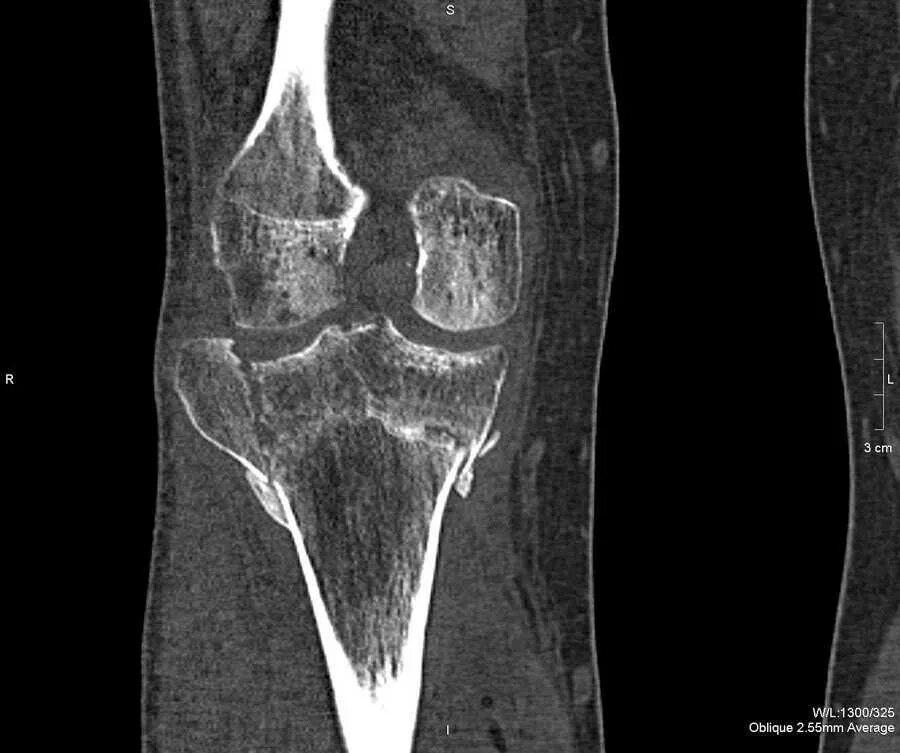

Кт суставов что показывает